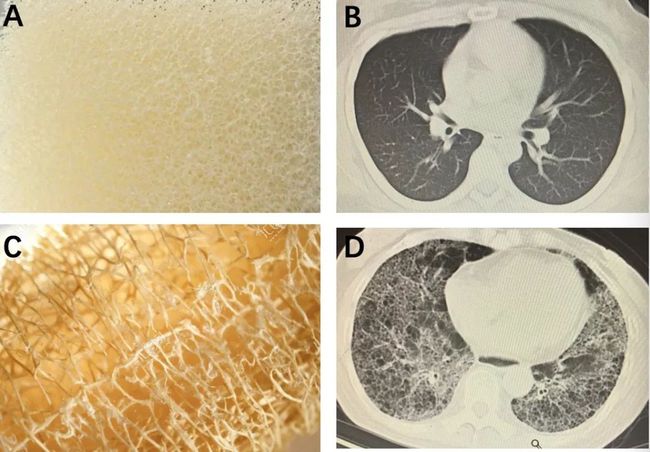

间质性肺疾病(ase, ILD) 是一类复杂的、较难明确病因的,主要累及肺间质、肺泡和(或)细支气管的弥漫性肺部疾病,IPF大约占ILD的20%。PF-ILD,也被描述为具有进行性表型的慢性纤维化间质性肺疾病,是一组以慢性进行性纤维化性表型,自我维持的纤维化和肺功能持续恶化,同时伴随临床症状恶化、对治疗的反应较差并且生存期较短为特征的疾病。在ILD患者中,PF-ILD患者估计约占20%–30%

从目前这两种疾病的治疗手段上来看,尼达尼布或吡非尼酮的抗纤维化治疗可减缓肺功能下降,是IPF治疗的主要手段,且尼达尼布扩大了对PF-ILD治疗的适应症,成为第一个被批准用于治疗PF-ILD患者的药物,标志着PF-ILD治疗中的重大里程碑。虽然IPF直接的致病途径尚不明确,但肺纤维化的形成机理应该是肺泡上皮细胞损伤和修复的失调和重塑,许多促纤维化介质都有可能在IPF的发病机制中起重要作用,而PF-ILD也通过类似的机制发展——自我持续的细胞修复失调、成纤维细胞增殖机制和肺泡功能障碍。PDE4可通过特异性水解第二信使cAMP而调控促炎、抗炎细胞因子的产生,从而发挥一系列作用,因此PDE4也成为炎症性疾病的重要治疗靶点,PDE4抑制剂在抗纤维化方面的潜力亟待探索。